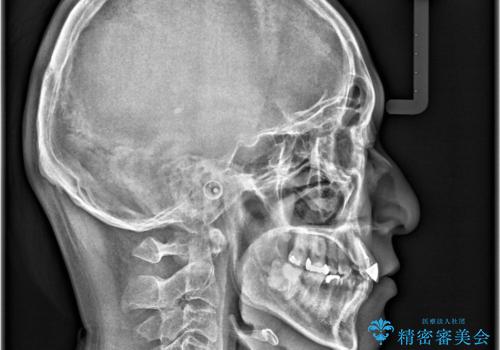

- 「八重歯と歯のでこぼこを治したい」を主訴に来院された患者様です。

歯は抜かずに奥歯の遠心移動とIPRで八重歯とでこぼこを改善しました。